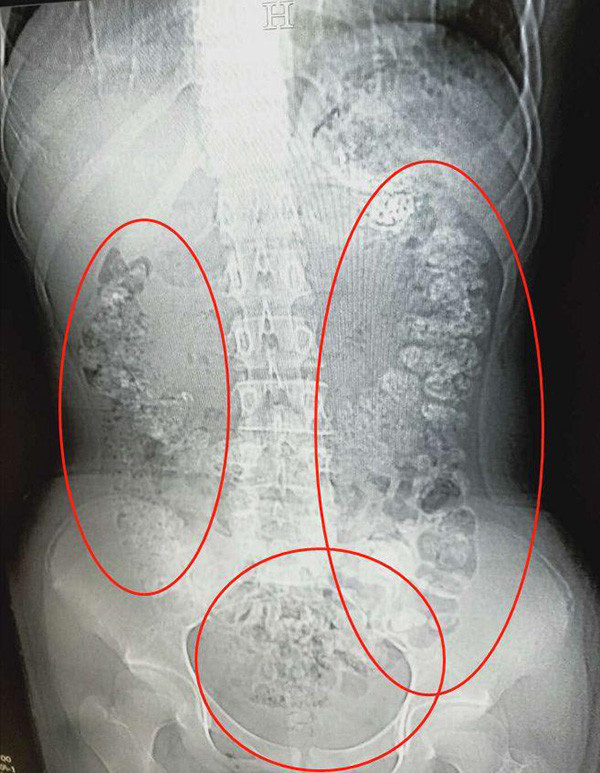

▼根據中國《澎湃新聞》的報導,這名14歲少女於5月28日在父母陪同下來到浙江諸暨市人民醫院急診。原來她已經連續5天都腹痛不已,不僅沒有排便更吃不下東西,當時醫師見她肚子鼓鼓的,於是安排了她做腹部 CT,結果發現患者的胃部、橫結腸、升結腸、降結腸、乙狀結腸一直到肛門,都佈滿了密密麻麻的顆粒陰影!

▼醫師馬上追問少女最近吃了什麼不易消化的食物,少女才支支吾吾的表示,自己5天前喝了珍珠奶茶。不過醫師推斷少女體內未消化珍珠的數量不像是喝一杯珍奶就能累積的,應該是近期都有喝了一段時間,因為害怕父母念她才會選擇隱瞞。最後醫師開了一些「潤腸通便」的藥物,協助她把未消化的「珍珠」排出體外。